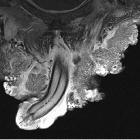

An

extraordinary case of Buschke–Lowenstein tumor: multiple localization, malignant transformation, and clinical insights—a case presentation and literature review. MRI image of the inguinal and penile lesions